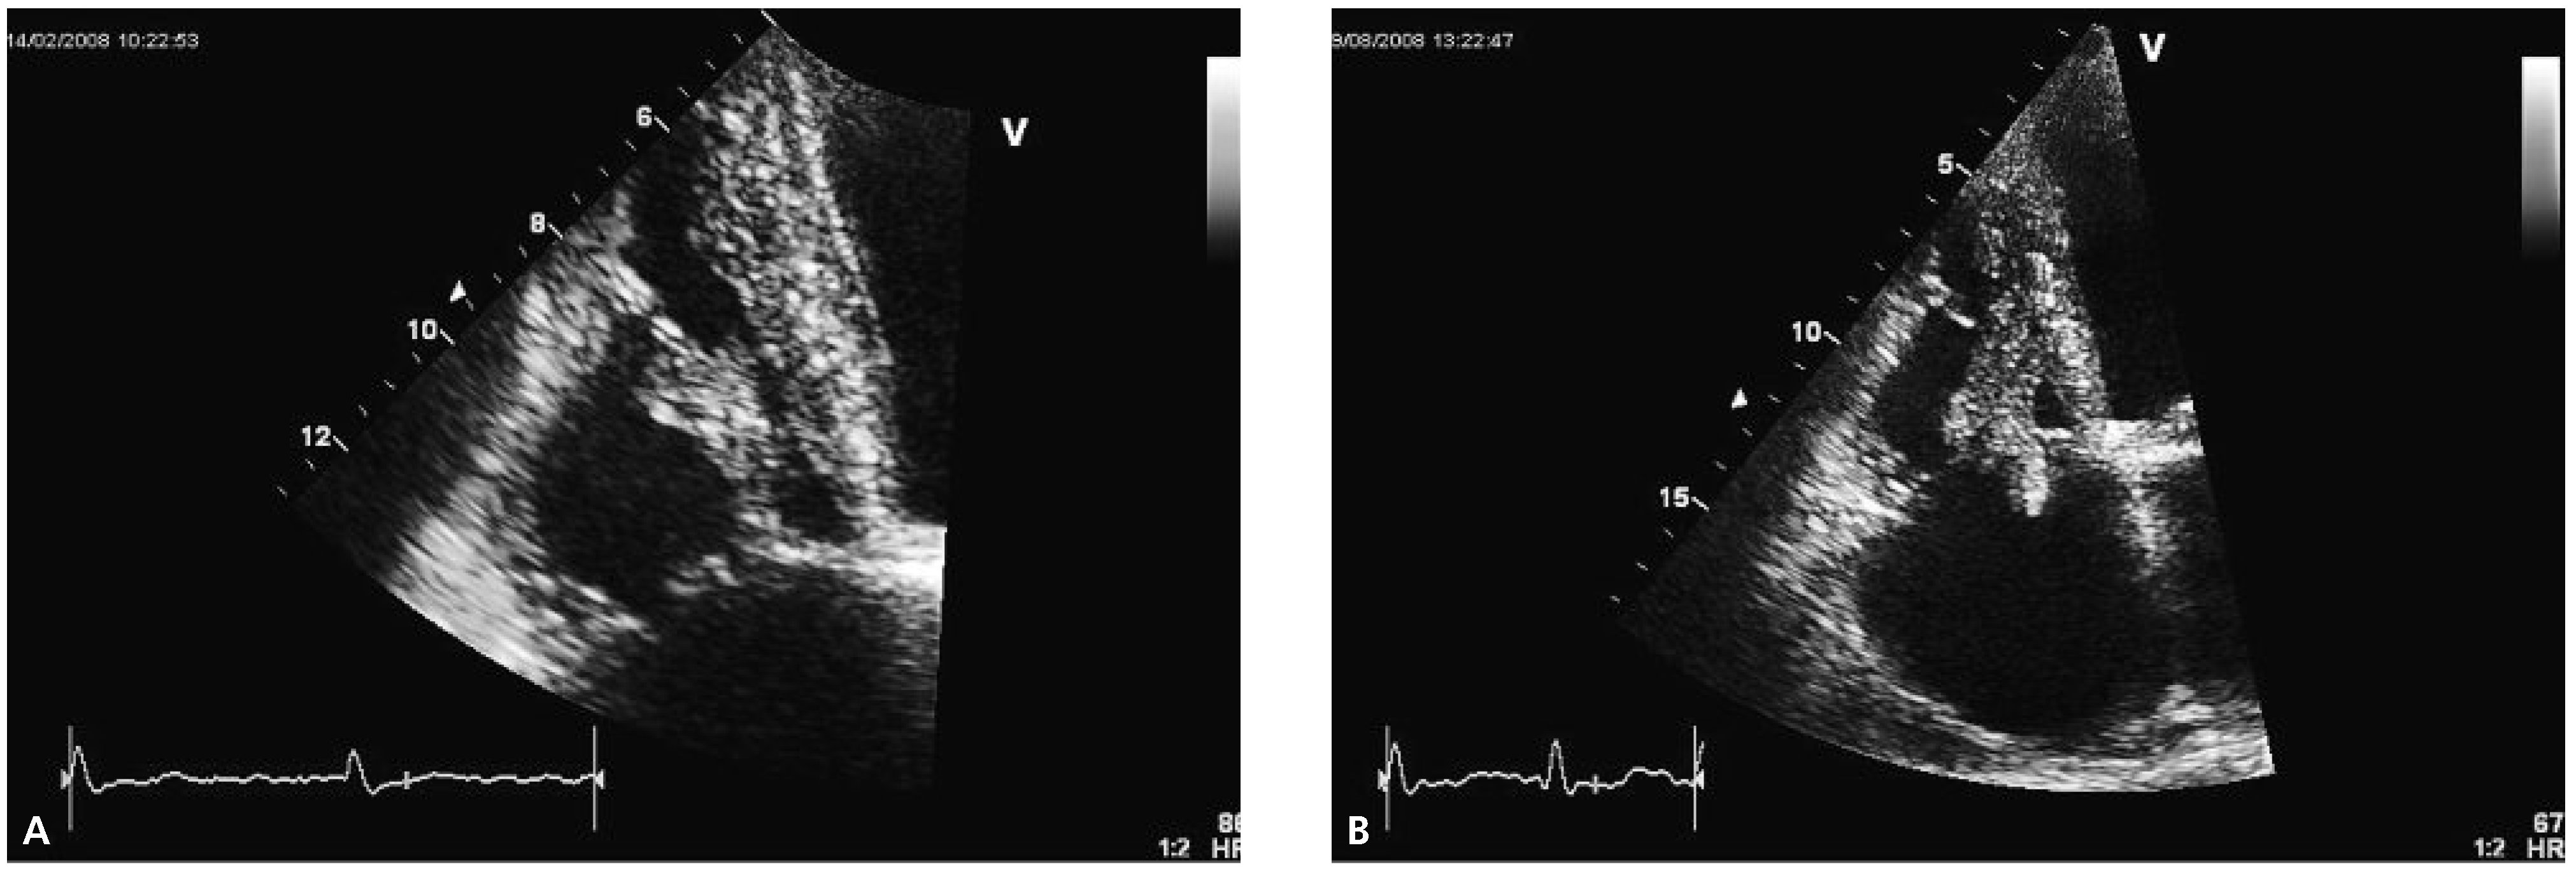

Echocardiography two months later revealed a slightly improved left ventricular ejection fraction (30–35%) and an obvious reduction in size of the thrombus (Figure 2A).

Figure 2.

Echocardiographic follow-up images. Note the increase in size and the prolapsing part of the thrombus in panel (B).

Follow-up echocardiography was performed again half a year later. At that time, the size of the right ventricle appeared normal whereas the systolic right ventricular function was still reduced (TAPSE 1.8 cm, TDI 9 cm/s). The thrombus had increased in size with new highly mobile parts prolapsing into the right atrium (Figure 2B). The patient passed away at home seven months later from an unknown reason.